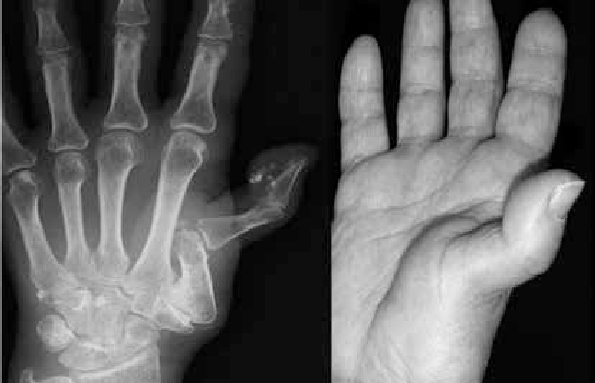

La degenerazione avviene in modo progressivo ed è quindi possibile distinguere degli stadi di malattia. Inizialmente, il sovraccarico, l'iperlassità legamentosa e/o i movimenti ripetitivi possono causare l'infiammazione della sinovia con versamento intrarticolare. Successivamente, inizia il processo di degenerazione della cartilagine per cui la rima articolare si riduce e compaiono osteofiti (neoformazioni ossee che impediscono ulteriormente il corretto movimento articolare). Nelle fasi più avanzate poi, la base del primo metacarpo si sublussa andando in direzione dorsale e, di conseguenza, modificando la biomeccanica articolare. Infine, nei casi più gravi si può arrivare all'anchilosi dell'articolazione nella posizione di sublussazione con la comparsa del "pollice a zeta".

Il quadro clinico di questa patologia si caratterizza per la rigidità articolare, la difficoltà di movimento e il dolore localizzato alla base del pollice, che compare all'inizio delle attività e persiste anche a riposo arrivando, talvolta, a rendere difficoltoso lo svolgimento delle normali attività quotidiane. La diagnosi viene eseguita attraverso l'esame clinico, con il supporto di radiografie per verificare lo stato di salute articolare. Il trattamento è, nella maggior parte dei casi, di tipo conservativo con l'impiego di tutori per immobilizzare e scaricare l'articolazione, farmaci e terapie fisiche antinfiammatorie. La chirurgia viene scelta nei casi più gravi che presentano soprattutto forte dolore. Gli interventi possibili sono molteplici in base all'età, al quadro clinico e alle esigenze del paziente. La protesi, che in altre articolazioni come ginocchio e anca, è la scelta più efficace, in questo caso non garantisce risultati eccellenti a causa delle ridotte dimensioni dell'articolazione e dell'alta mobilità della stessa. La fisioterapia può essere utile soprattutto in seguito alla chirurgia per riprendere l'attività lavorativa in breve tempo e in sicurezza.